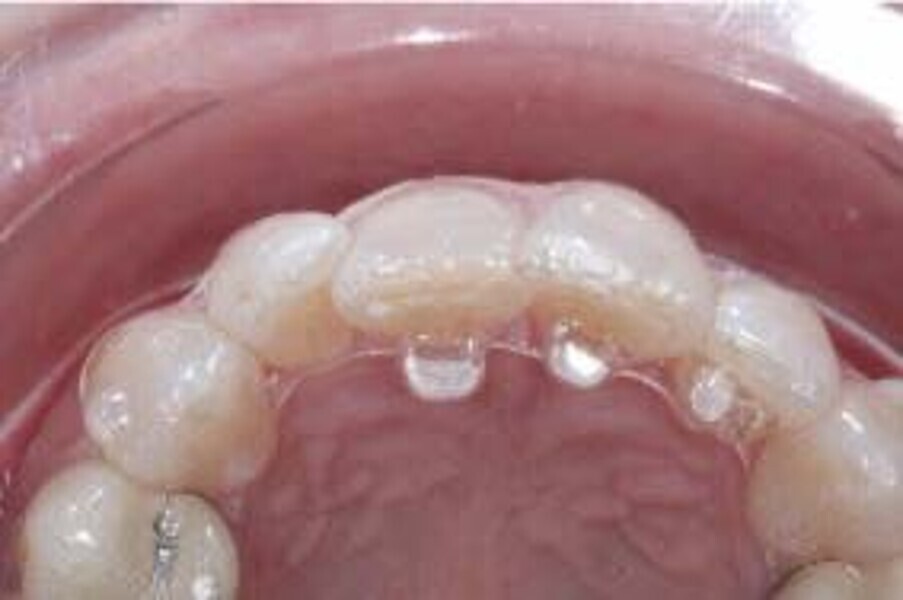

To properly correct deep bite malocclusion with aligners, the Invisalign system (Align Technology) has introduced precision bite ramps, anterior customised bite turbos, embedded into the aligners, and these are available for the lingual surface of the maxillary central and lateral incisors or of the maxillary canines. This feature does not require composite filling like for traditional attachments; it is a lingual extension of the aligner (maximum palatal extension of 3 mm) that creates premature anterior contacts and posterior disocclusion. The ramps are planned to move, stage by stage, in a more occlusal direction, creating the necessary posterior occlusal space to permit lateral and posterior teeth to extrude relatively. The ramps need to be combined with two other features: extrusion attachments on lateral teeth and mandibular incisor pressure areas, a lingual pressure point designed to exert intrusive forces following the long axis of the incisors more effectively. In this way, the levelling of the mandibular curve of Spee will be more reliable, combining two reciprocal movements in two different parts of the arch, anterior intrusion, and posterior extrusion, as indicated in the literature (Figs. 1–8).6, 7

The digital treatment plan (ClinCheck) provided 12 aligners for the maxillary arch and 17 for the mandibular arch. The treatment objectives were focused on coupled vertical movements of posterior extrusion and anterior intrusion by means of bite ramps, providing for posterior disocclusion and anterior intrusion of mandibular teeth by means of extrusion attachments needed for mandibular arch levelling. The maxillary and mandibular incisors were proclined to level the upper and lower curve of Spee and to support the flat profile and the lips. Class II elastics were planned to support mandibular proclination and heavy posterior occlusal contacts with relative posterior extrusion. Lateral and posterior maxillary torque were planned to be close to 0°, to achieve wider arch design and ideal intercuspation. No digital over-engineering was planned in the set-up. Because of the age of the patient, the aligners were changed every ten days for a treatment time of less than six months. At the end of the first stage of aligners (Figs. 20–24), an additional stage was planned to improve molar intercuspation without elastics with a digital plan of five further aligners. This brought the total treatment time to 7.5 months since the additional aligners were changed every week.